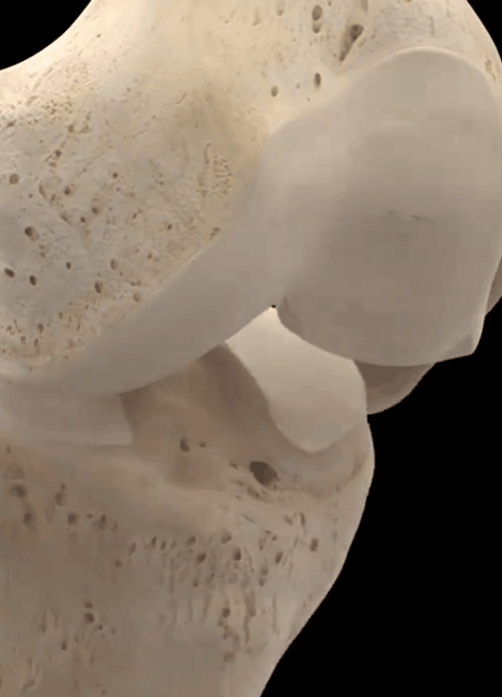

Wie Sie auf dem Bild unten sehen können, ist es typisch, dass sich die Gelenke entwickelt habenSichtbare Lücken, schmale Knochenbildung, einhergehend mit einer schwereren GelenkosteoporoseWenn ein solcher Patient offensichtliche Missempfindungen und Schmerzen hat, wird der Patient durch intraartikuläre Injektionen von Natriumvitrat oder ständige orale Analgetika, die dem Patienten nicht wirklich helfen, das Problem zu lösen, in starke Schmerzen versetzt.

In unseren Kniegelenken ist die Gelenkfläche mit feinem, glattem Knorpel überzogen, damit sie sich reibungslos bewegen kann. Wenn die Gelenkfläche aufgrund von Verletzungen oder Überbeanspruchung abgenutzt ist, wird sie uneben, und der Knochen gleitet bei der Bewegung des Gelenks auf der unebenen Fläche, was zu einem Klappern führt. Bei der Bewegung des Gelenks gleitet der Knochen auf der unebenen Gelenkfläche und es entsteht ein klapperndes Geräusch, das von starken Schmerzen begleitet sein kann.

- Frikativ--Wenn der Gelenkknorpel stark abgenutzt ist, verlieren die Enden der subchondralen Knochen den Knorpelschutz, und bei direkter Reibung ertönt ein leises, heiseres Reibegeräusch; die in der Gelenkhöhle umherwandernden Knorpeltrümmer verursachen auch leicht ein Einklemmen, was zu einem Gelenkreibungsgeräusch führt. Die Patienten sollten es von einem normalen physiologischen Knacken unterscheiden, das Beurteilungskriterium ist sehr einfach, ein pathologisches Knacken wird oft von Gelenkbeschwerden begleitet.